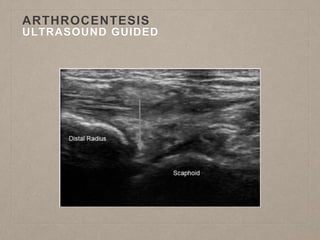

ARTHROCENTESIS

ULTRASOUND GUIDED